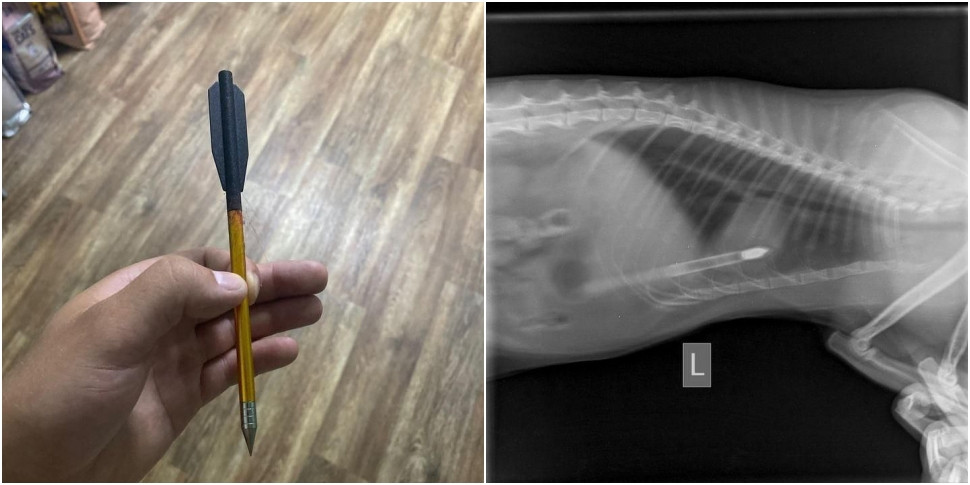

— Ребята приезжают, я осматриваю котика — и что вы думаете? В котике торчит стрела от арбалета — 17 сантиметров, — которая прошла ему через два легких, — говорит на видео врач.

Сообщается, что кот идет на поправку, а милиция ищет живодера.